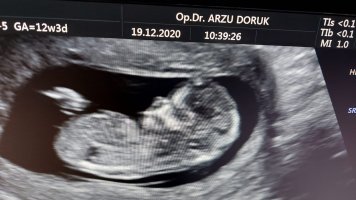

• 60655A4A-BAF1-4EBB-9F5F-EEAFE74B8B36.jpeg

60655A4A-BAF1-4EBB-9F5F-EEAFE74B8B36.jpeg

136,1 KB · Görüntüleme: 1.325